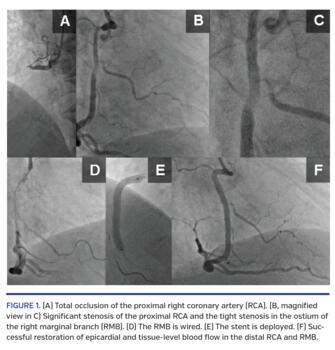

A 59-year-old male was admitted due to suspicion of myocardial infarction. Left-sided 12-lead electrocardiogram (ECG) revealed ST-elevation in II, III, aVF; inferior ST-segment elevation myocardial infarction with right ventricle (RV) involvement was suspected and right-sided ECG revealed ST elevation in V3R-V6R. Coronary angiography revealed acute occlusion of the proximal right coronary artery (RCA) (Figure 1A). A guidewire was introduced into the distal RCA and manual thrombus aspiration (VMax catheter; Stron Medical) restored normal epicardial blood flow. Significant stenosis of the proximal RCA and a tight ostial stenosis of the right marginal branch (RMB) originating within the prime occlusion site were visualized (Figures 1B and 1C). Another guidewire was introduced into the RMB to mechanically protect its lumen from occlusion with displaced thrombus (Figures 1D and 1E). A 3.5 x 35 mm Xience drug-eluting stent (Abbott) was successfully implanted in the proximal RCA (Figure 1E). Finally, normal blood flow was restored in both the distal RCA and RMB (Figure 1F). Left-sided and right-sided postprocedural ECG revealed complete normalization of ST elevation. Despite persistent proximal RCA occlusion, RV function may recover over time, but the goal is to provide successful and timely restoration of patency in the RMB. This case demonstrates the effectiveness of an extra guidewire in the RMB lumen to provide mechanical protection from displaced thrombus, which frequently occurs during proximal RCA stenting.